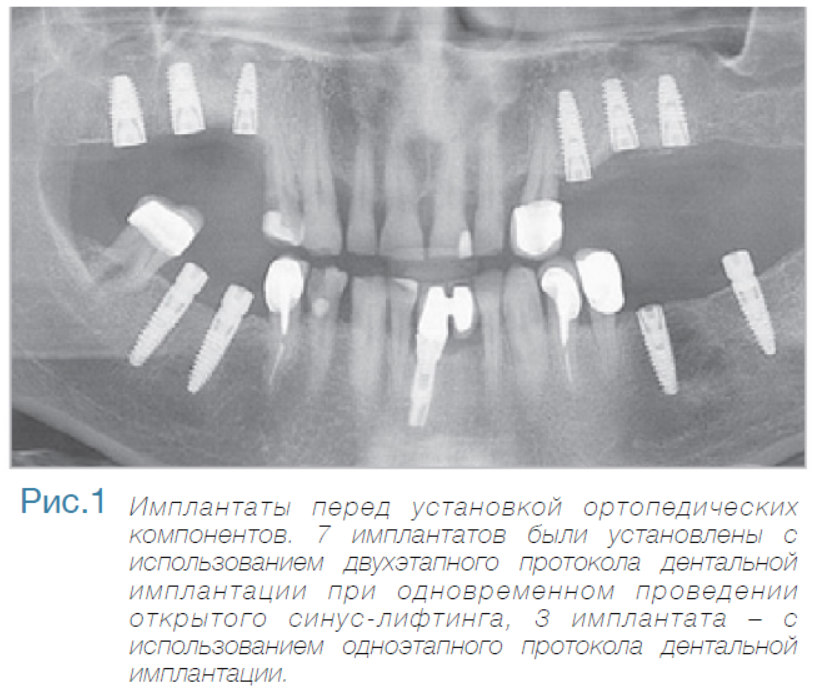

В частной практике (LS) были установлены 30 имплантатов MIS С1 (конических, с внутренним коническим соединением с переключением платформ). В исследовании приняли участие 10 мужчин и 8 женщин, при этом средний возраст пациентов составил 57 лет (возрастной диапазон 35-75 лет). 6 пациентов были курильщиками. 9 имплантатов установили на верхней челюсти, 21 – на нижней челюсти, 13 – во фронтальной области, 17 — в области боковых зубов. Для 10 имплантатов был использован одноэтапный протокол имплантации, для 20 — двухэтапный. Керамические реставрации были зафиксированы на имплантатах через 3 (18) и 6 (12) месяцев после их установки. Уровень маргинальной костной ткани с мезиальной и дистальной сторон имплантатов измерили с помощью рентгенограмм непосредственно в день установки дентальных имплантатов (исходный уровень), в день раскрытия (через 3 или 6 месяцев после установки) и ровно через год после проведения дентальной имплантации.